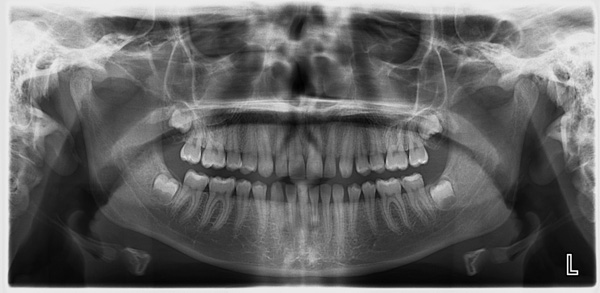

Using the most advanced orthodontic technology possible is just as important as staying up-to-date on the latest treatment techniques. Because our practice is dedicated to providing you with the safest and most convenient treatment options available, we utilize advanced digital X-ray technology in our office.

Digital X-rays provide several advanced imaging options designed to save time, provide clearer dental photos, and expose patients to less radiation than traditional X-ray technology.